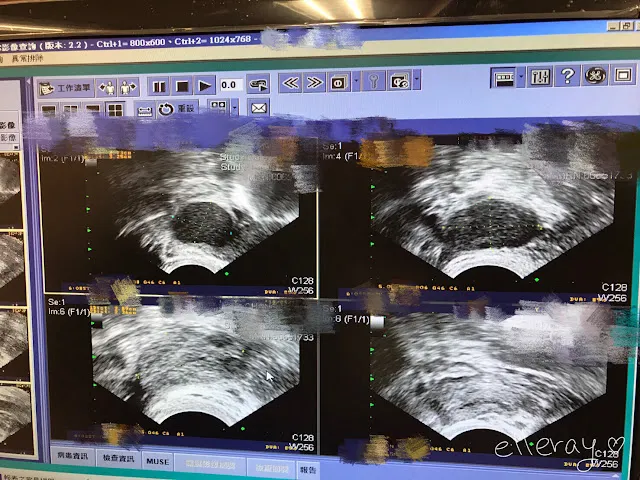

換好衣服,與Ray到隔壁領藥,恰好遇到江醫師,她來幫我們處理批價問題,(原本自費,後來發現這個手術可健保給付,所以只花了493元),並告訴我抽吸手術相當適合我,成效非常好,還把超音波圖的前後對比讓我看,兩側囊腫完全消失,據說抽了兩百CC的血水,看得既驚心又開心。返家之後,除了覺得下腹部像生理期時的悶脹外,沒有不舒服,吃了一點東西,吃了藥休息一下,原以為關卡已經結束了,殊不知還有最後一道難題。